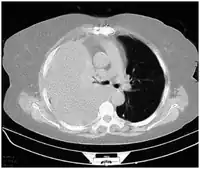

-

Development of hemothorax following lung lesion biopsy -

Showing a massive left-sided hemothorax -

Right showing a massive right hemothorax

A chest X-ray is the most common technique used to diagnosis a hemothorax.[23] X-rays should ideally be taken in an upright position (an erect chest X-ray), but may be performed with the person lying on their back (supine) if an erect chest X-ray is not feasible. On an erect chest X-ray, a hemothorax is suggested by blunting of the costophrenic angle or partial or complete opacification of the affected half of the thorax. On a supine film the blood tends to layer in the pleural space, but can be appreciated as a haziness of one half of the thorax relative to the other.[5] A small hemothorax may be missed on a chest X-ray as several hundred milliliters of blood can be hidden by the diaphragm and abdominal viscera on an erect film. Supine X-rays are even less sensitive and as much as one liter of blood can be missed on a supine film.[24]

Computed tomography (CT or CAT) scans may be useful for diagnosing retained hemothorax as this form of imaging can detect much smaller amounts of fluid than a plain chest X-ray. However, CT is less used as a primary means of diagnosis within the trauma setting, as these scans require a critically ill person to be transported to a scanner, are slower, and require the subject to remain supine.[23][26]